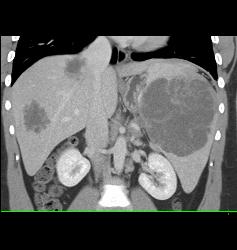

Lymphoma Involves Liver and Spleen